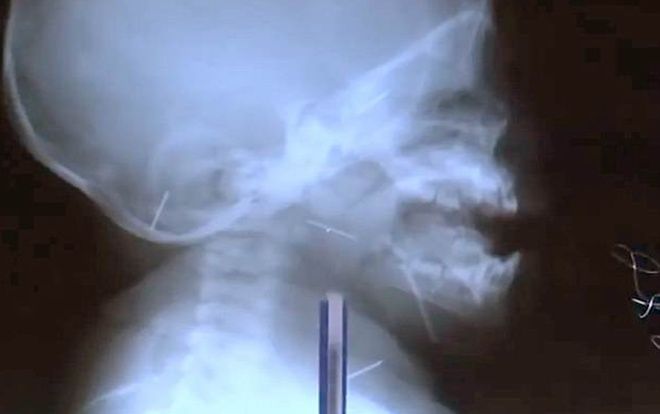

Một bé trai 9 tháng ở quốc gia Trung Á Tajikistan đang vật lộn giành sự sống sau khi bác sĩ tìm thấy 10 cây kim trong cơ thể em.